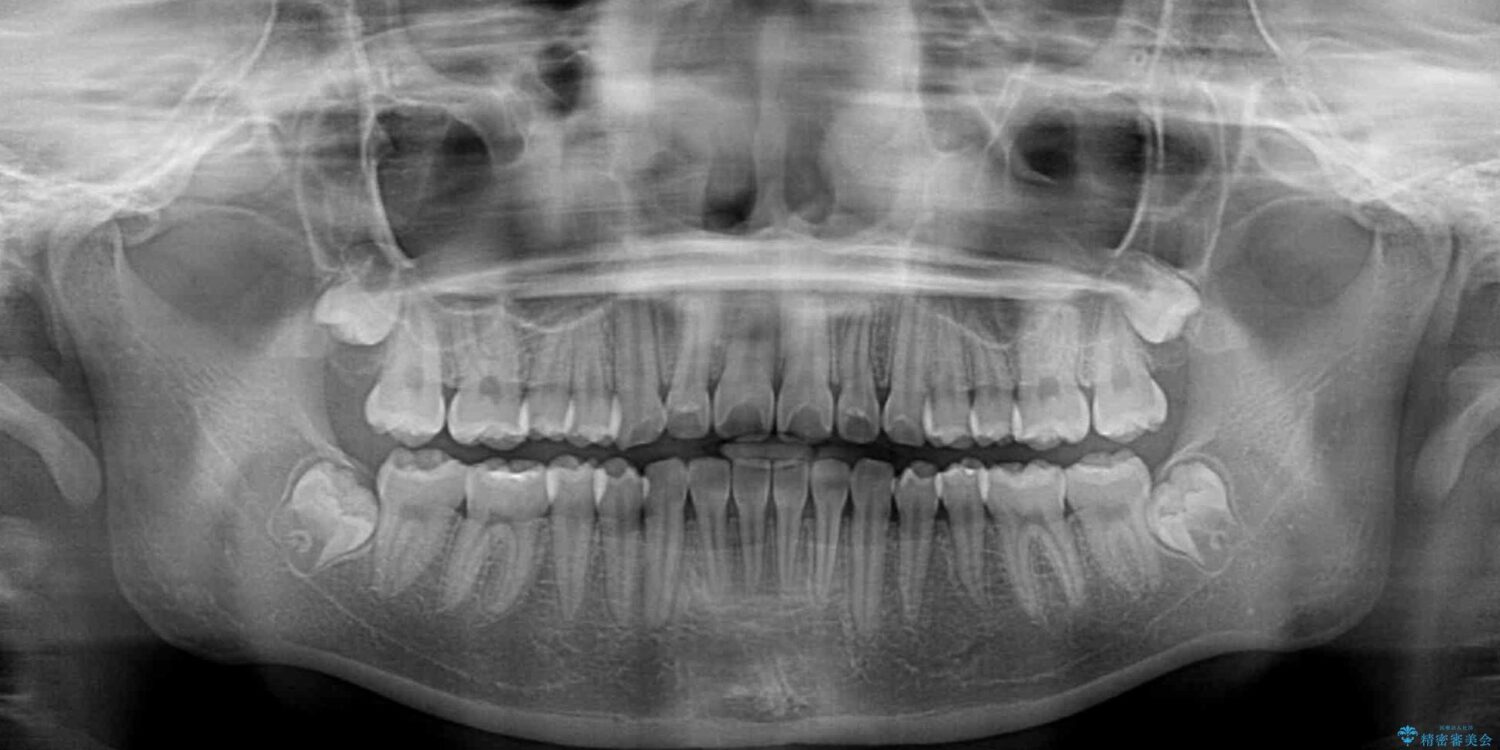

治療前

• インビザラインは使える自信がない ワイヤー装置にて矯正治療 治療前画像